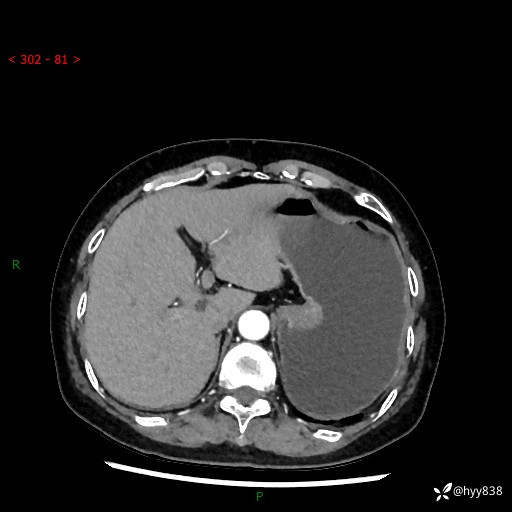

辅助检查:CT

胃CT平扫+增强(动脉期+静脉期)

三期CT值:46hu 58hu 75hu